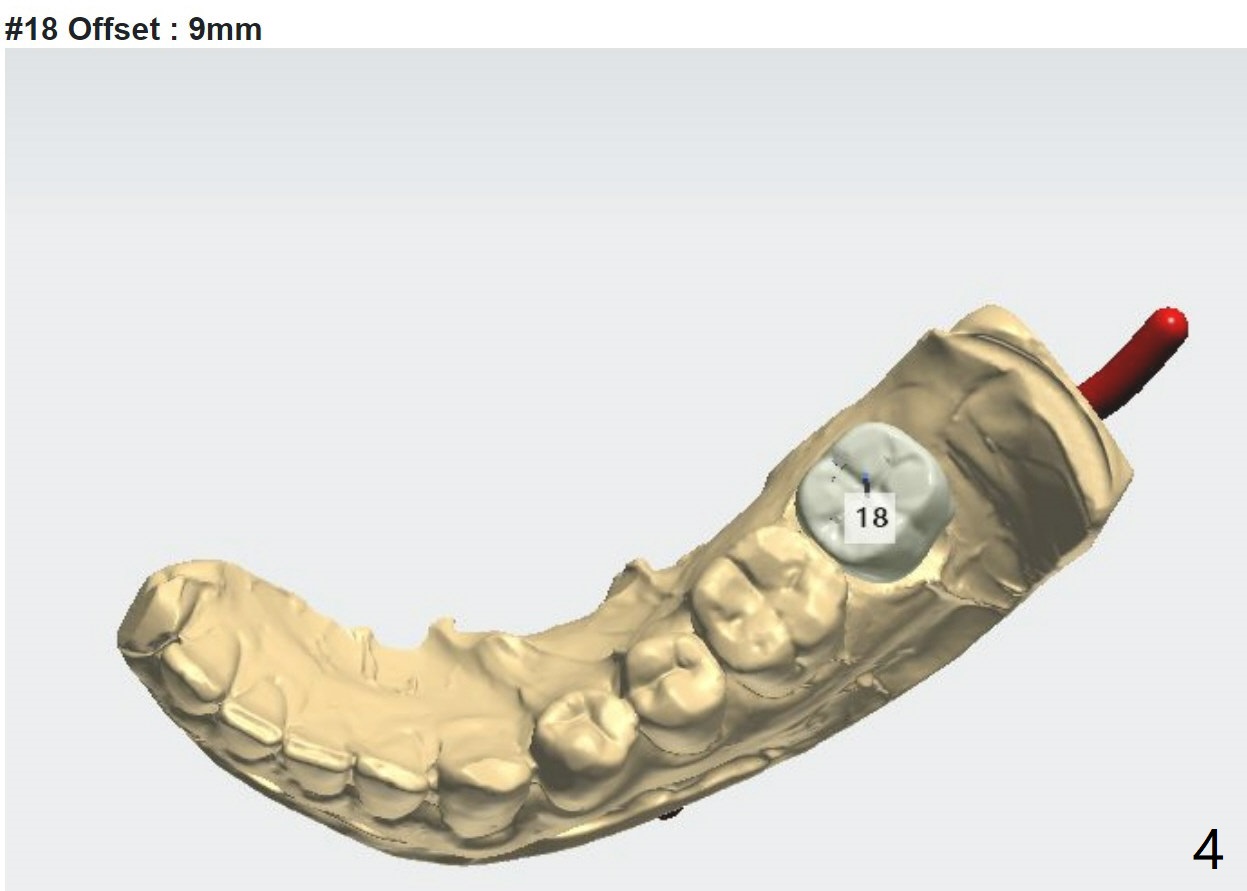

9 mm offset

A 35-year-old man has severe caries #18 D due to 3rd molar impaction. There appears no bone loss at #18. Small amount of sticky bone with PRF membrane should be prepared.